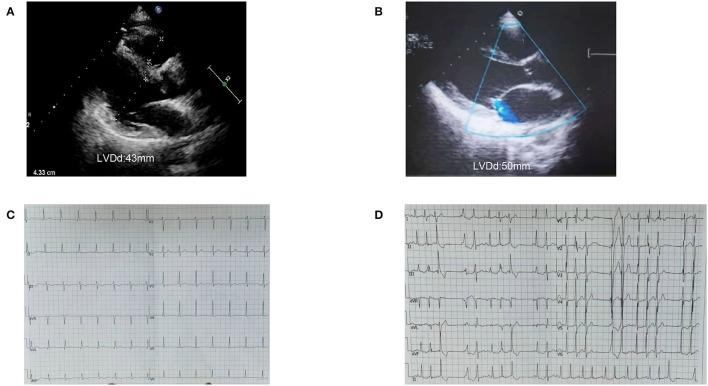

We report a 3-generation family with c.611 C>A rare variant, whose clinical characteristics are dilated cardiomyopathy (DCM) combined with multifocal ectopic Purkinje-related premature contractions (MEPPC). We tried to explain why the same variant carriers had different phenotypes.

Information was collected from 15 people in this family, 8 of whom had genetic testing. The variant was present in all patients of this family, whose clinical features showed DCM combined with MEPPC. The proband's children developed DCM and MEPPC in their childhood. They both carried a p.A204E mutation from their mother and a mutation p.D372N from their father. The son did heart transplant and his heart was both dilated and thickened. The pathology confirmed the presence of glycogen accumulation in the myocardium, which were consistent with the diagnosis of syndrome.

我们报告一个携带c.611 C>A罕见变异的三代家系,其临床特征为扩张型心肌病(DCM)合并多灶性浦肯野相关室性早搏(MEPPC)。我们试图解释为何相同变异携带者具有不同表型。

从该家系15人中收集了信息,其中8人进行了基因检测。该变异存在于该家系所有患者中,其临床特征表现为DCM合并MEPPC。先证者的孩子在童年时患DCM和MEPPC。他们均从母亲那里遗传了p.A204E突变,从父亲那里遗传了p.D372N突变。儿子接受了心脏移植,其心脏既有扩张又有增厚。病理检查证实心肌中存在糖原蓄积,这与综合征的诊断相符。